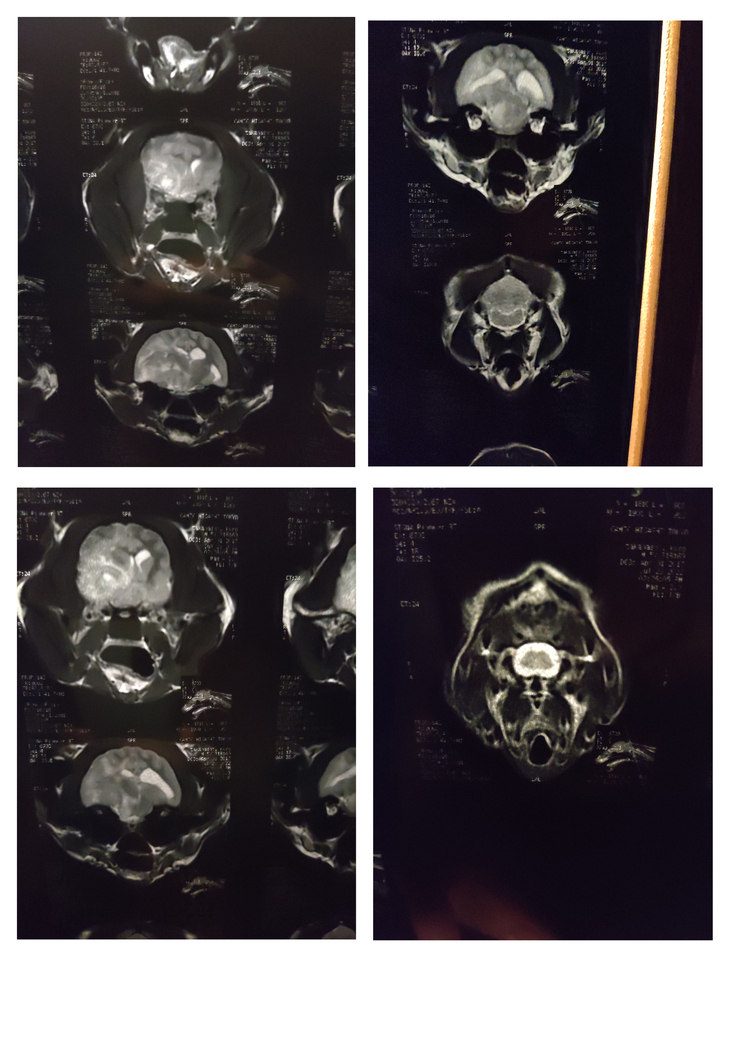

7/23 MRI検査で腫瘍が見つかる。

(病院より使用許諾取得済み)

MRI画像中の白い塊が腫瘍でかなり大きいとのことでした(病院より使用許諾取得済み)

右が術前、左が術後。術後の黒い空洞部分が腫瘍摘出箇所。(病院より使用許諾取得済み)